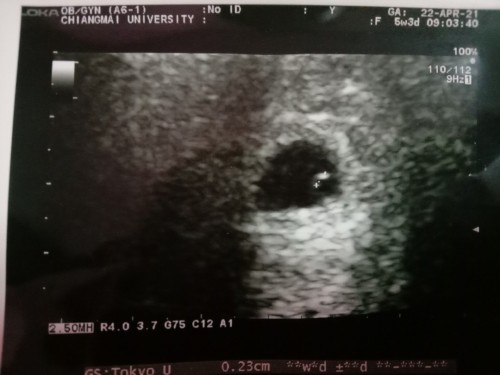

5 W 2 d ไม่เจอตัวอ่อน

ไปซาวมาแต่ไม่เจอตัวอ่อน. เจอแต่ถุงตั้งครรภ์ มีโอกาศมีตัวอ่อนไหมค่ะ หรือจะเป็นท้องลมค่ะ

ตอน6 w ก็เจอแค่ถุงตั้งครรภ์เล็กๆเหมือนกันค่ะ พึ่งมาเจอตัวอ่อนพร้อมเสียงหัวใจตอน8w

5w ไม่เจอเหมือนกันจ้า มาเจอตอน7w เห็นชัดเลยค่ะ ตอนนี้12w ตัวโตแข็งแรงปกติดีค่ะ

5 วีคจ้า เจอแต่ถุงตั้งครรภ์เหมือนกันค่ะ หมอนัดอีก 2 สัปดาห์ ☺️